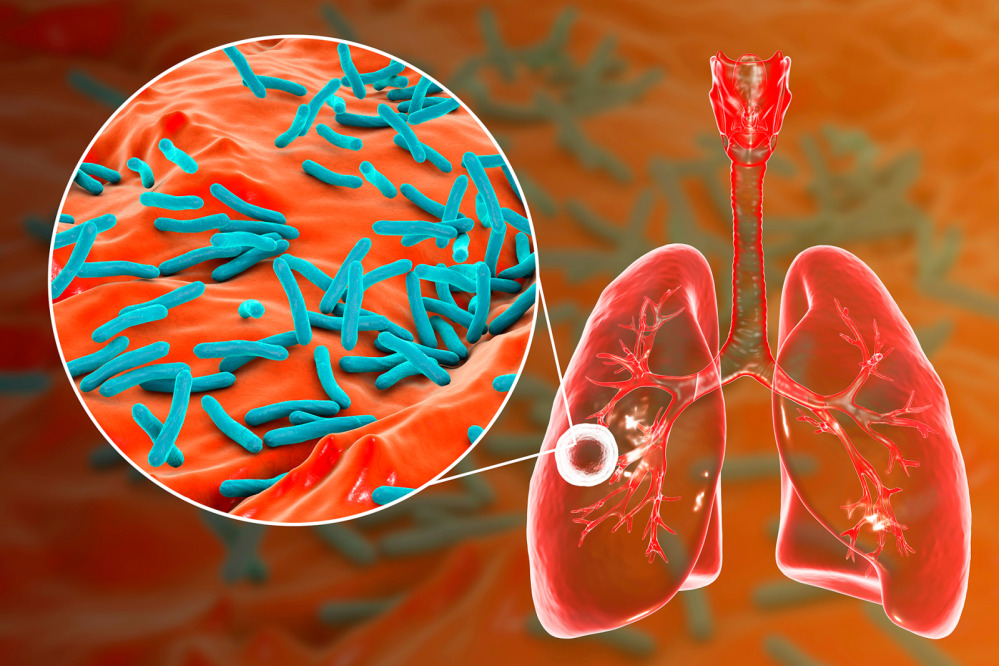

A Organização Mundial da Saúde (OMS) publicou um novo relatório sobre tuberculose revelando que aproximadamente 8,2 milhões de pessoas foram diagnosticadas com TB em 2023 — o maior número registrado desde que a OMS começou o monitoramento global da TB em 1995. Isso representa um aumento notável de 7,5 milhões relatados em 2022, colocando a TB novamente como a principal causa de morte por doença infecciosa em 2023, superando a COVID-19.

Enquanto o número de mortes relacionadas à TB diminuiu de 1,32 milhão em 2022 para 1,25 milhão em 2023, o número total de pessoas adoecendo com TB aumentou ligeiramente para uma estimativa de 10,8 milhões em 2023.

Com a doença afetando desproporcionalmente pessoas em 30 países de alta carga, Índia (26%), Indonésia (10%), China (6,8%), Filipinas (6,8%) e Paquistão (6,3%) juntos foram responsáveis por 56% da carga global de TB.

No entanto, a TB multirresistente continua sendo uma crise de saúde pública.

As taxas de sucesso do tratamento para TB multirresistente ou resistente à rifampicina (TB-MDR/RR) agora atingiram 68%. Mas, das 400.000 pessoas que se estima terem desenvolvido TB-MDR/RR, apenas 44% foram diagnosticadas e tratadas em 2023.

Um número significativo de novos casos de TB é causado por 5 principais fatores de risco: desnutrição, infecção por HIV, transtornos por uso de álcool, tabagismo (especialmente entre homens) e diabetes